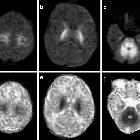

MRI

MRI brain may show the characteristic pattern of edema present in MSUD. Two forms of edema may be seen in MSUD:

- intramyelinic edema: believed to be from myelin splitting due to accumulation of branched-chain key acids and water molecules between layers of myelin

- vasogenic edema: usually due to disruption of the blood-brain barrier during an acute metabolic crisis or decompensation

Signal characteristics include:

- T1: low signal intensity

- predominantly in the cerebellar white matter, cerebral peduncles, posterior limb of the internal capsule, thalami, globe pallidi, perirolandic cerebral white matter and dorsal brainstem

- T2: high signal intensity

- in the locations described above

- DWI: the posterior limbs of the internal capsules and optic radiations and the central corticospinal tracts within the cerebral hemispheres exhibit high diffusion signal

- MR spectroscopy: single-voxel proton MR spectroscopy may show the presence of branched-chain amino acids and branched-chain alpha-keto acids resonating at 0.9-1.0 ppm, especially during a metabolic crisis